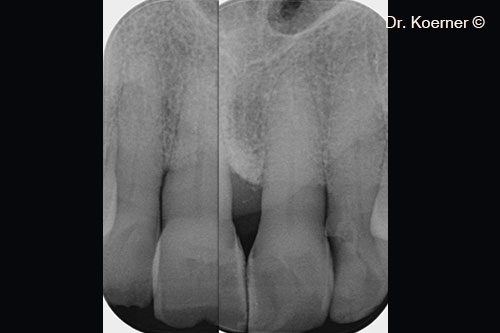

Chụp X-quang ban đầu

Tình trạng chụp X-quang 4 tháng sau phẫu thuật với nẹp cố định.

Tình trạng chụp X-quang 10 năm sau phẫu thuật.